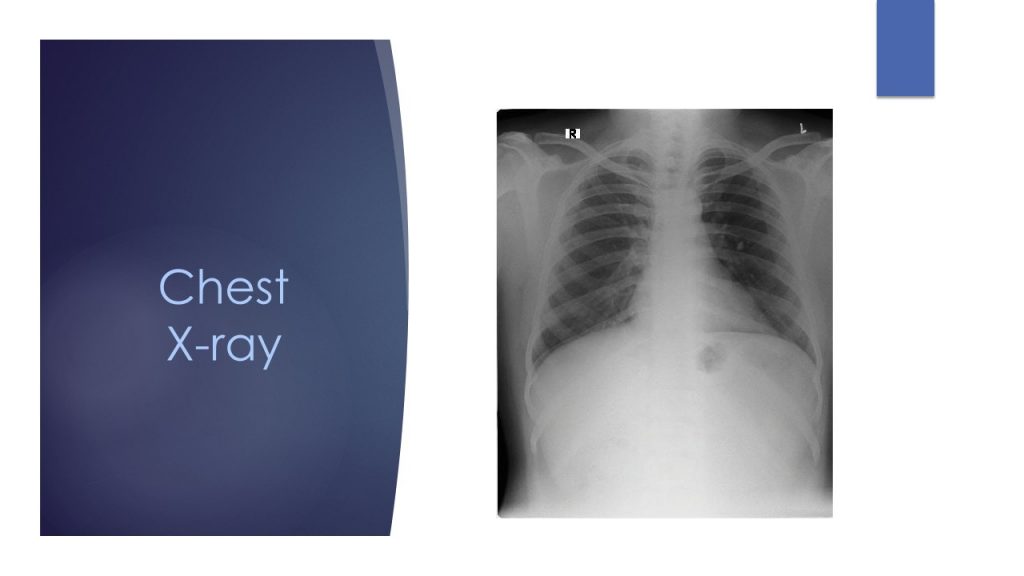

The middle-aged male patient had a 6-month history of symmetric arthritis (predominantly involving the lower limb), inflammatory back pain, episodes of recurrent diarrhea, and one previous hospital admission for diarrhea, which led to reactive arthritis. He had other systemic features like fever and vague abdominal discomfort. His inflammatory parameters were significantly elevated, though the rheumatoid factor and ANA were negative. Chest X-ray was normal and pelvis AP view indicated bilateral sacroiliitis.